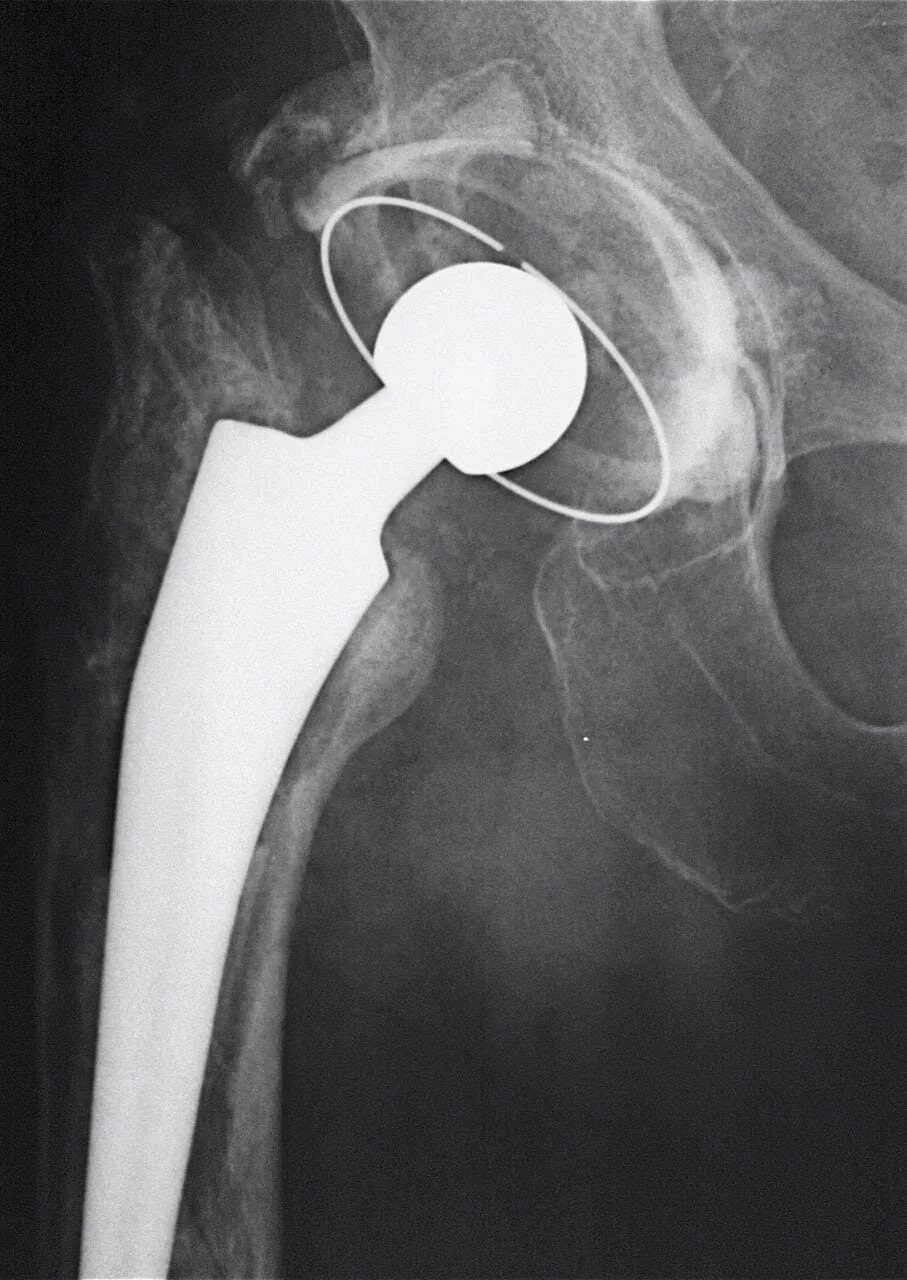

Подготовка к замене тазобедренного